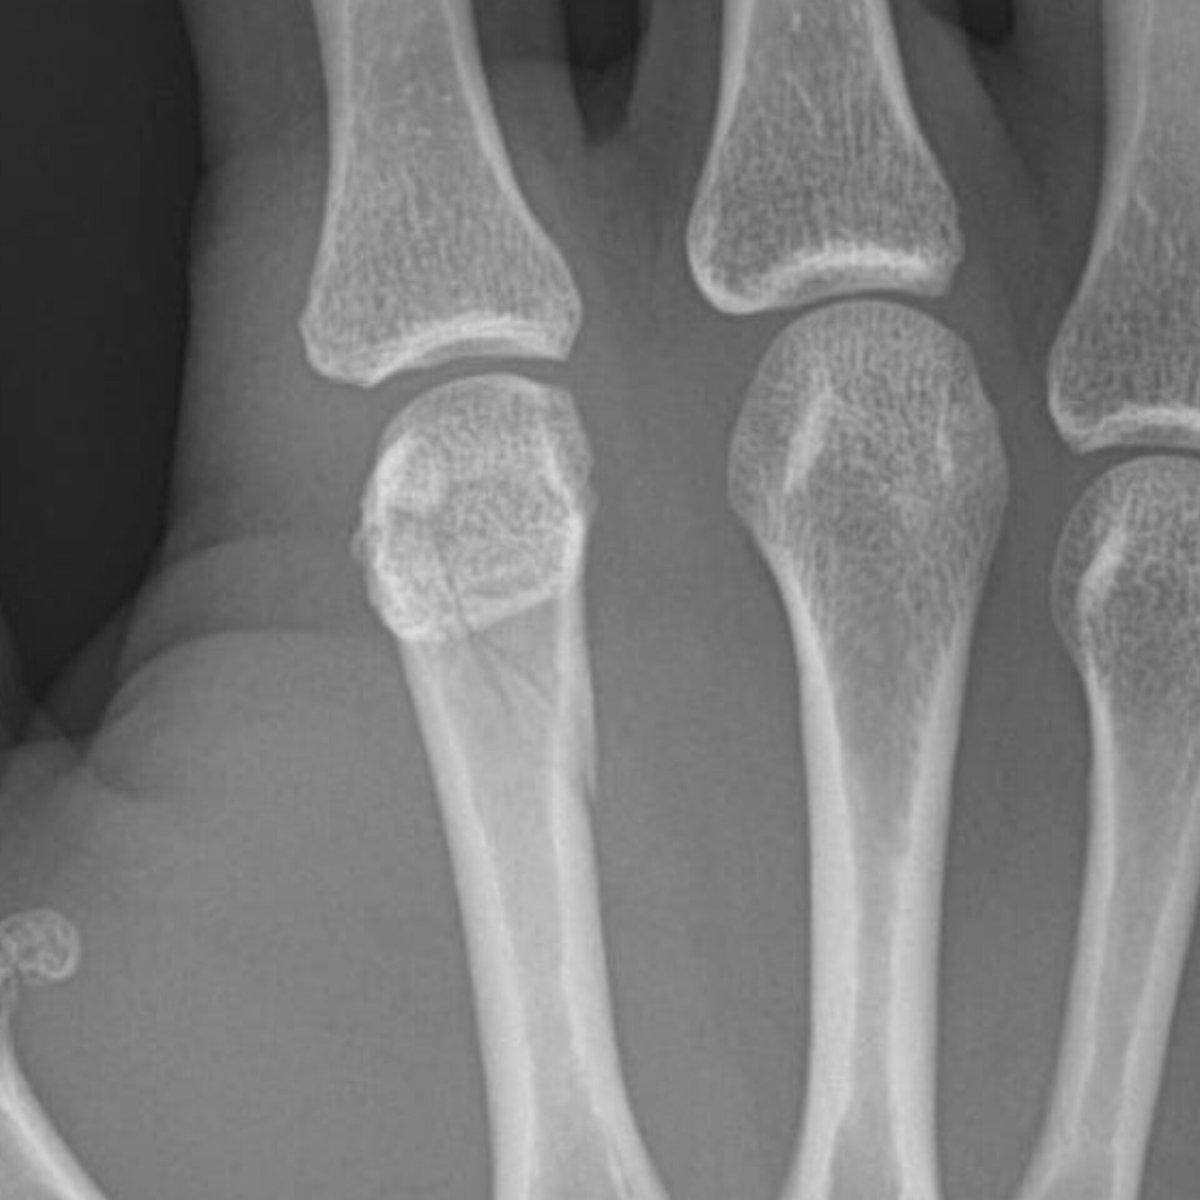

Informes confirman una FRACTURA en el segundo metacarpiano de la mano (hueso del dedo índice) tras el demoledor nocaut que sufrió en apenas 1 minuto y 22 segundos. 😱

El cantante mostró las radiografías que muestran la gravedad de la lesión.